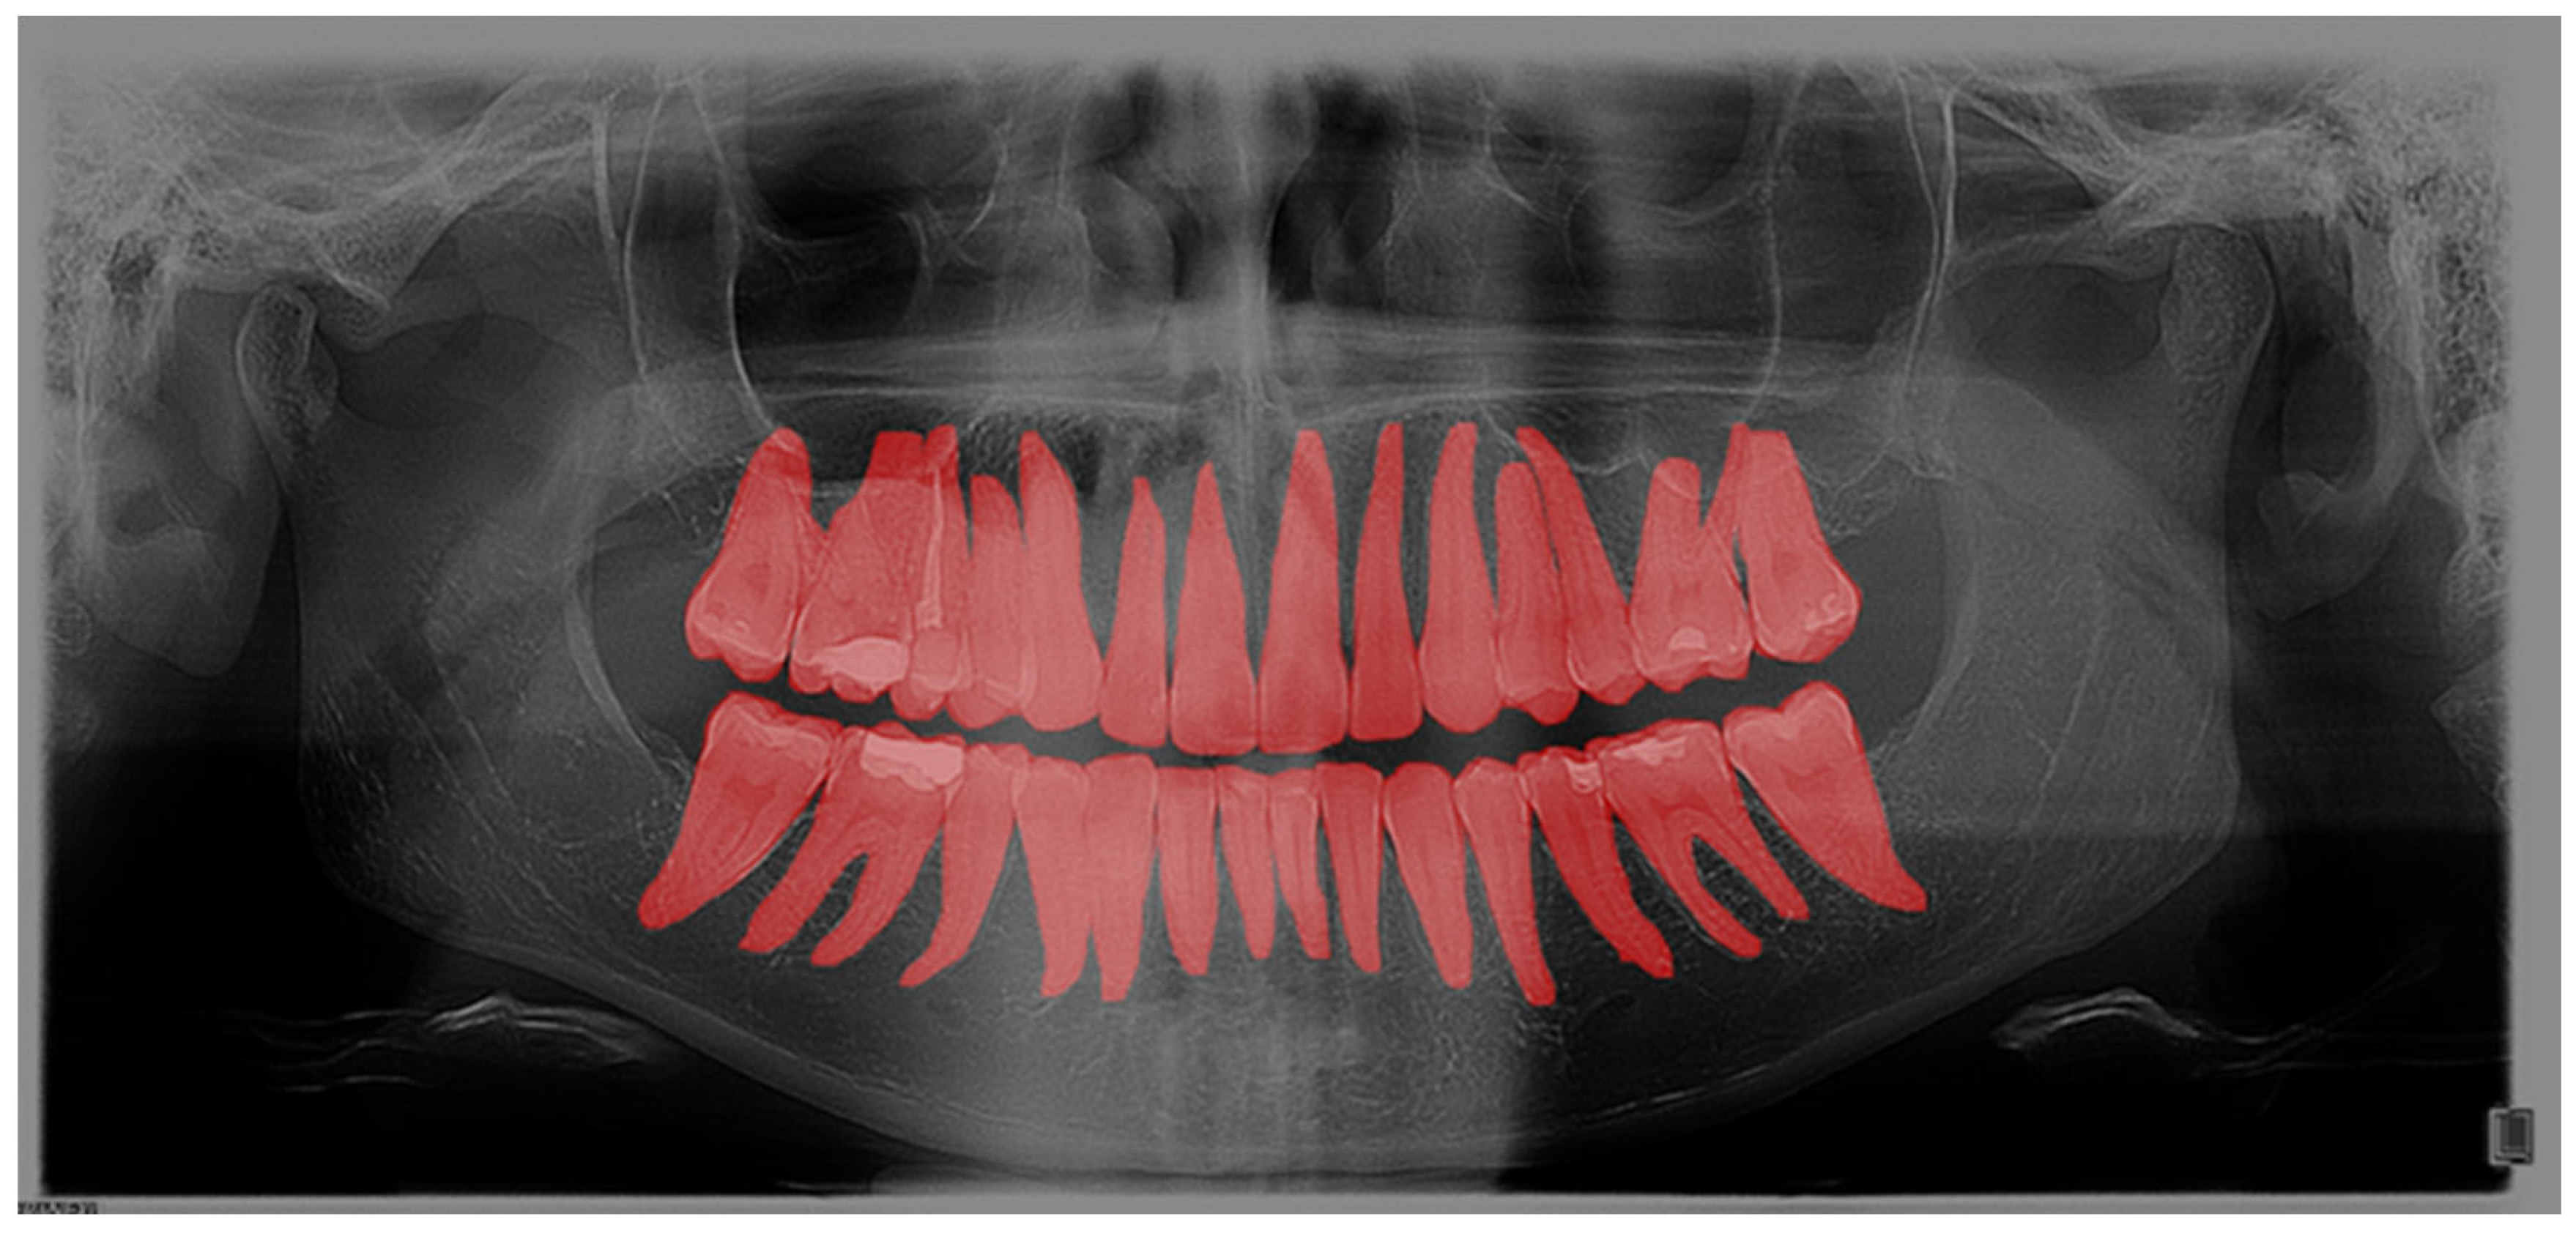

Furthermore, the findings were assessed across the complete OPGs, as well as in relation to segmented teeth (teeth separated from adjacent structures) and individual teeth. These individual teeth were marked in bounding boxes where the most prominent pixels were used as box margins (Figure 3).

Figure 3. Bounding box generated based on the segmented tooth marginal pixels.